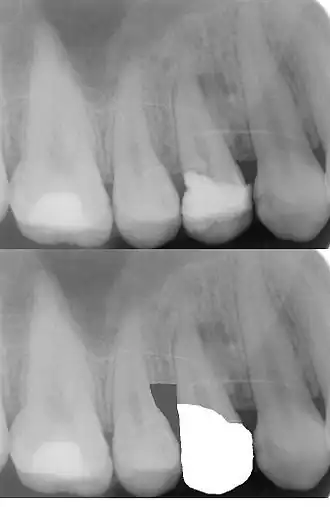

Abgesehen von der Wiederherstellung eines ausreichenden Zahnfleischsaums trägt der Ferrule-Effekt zur Stabilität der künstlichen Zahnkrone bei.[6] Umfasst die zukünftige künstliche Zahnkrone den Zahn nicht bandförmig, steigt die Frakturgefahr eines wurzelbehandelten Zahnes.[6] In der oberen Röntgenaufnahme sieht man die an den Alveolarknochen angrenzende Zahnfüllung (weiß = röntgenopak). Auf der unteren Röntgenaufnahme sieht man die Kronenversorgung des Zahnes nach einer chirurgischen Kronenverlängerung im distalen Bereich, das heißt nach der Entfernung des Knochenseptums. (Die untere Röntgenaufnahme ist keine Originalaufnahme. Sie wurde digital bearbeitet, um das Prinzip der Kronenverlängerung aufzuzeigen).